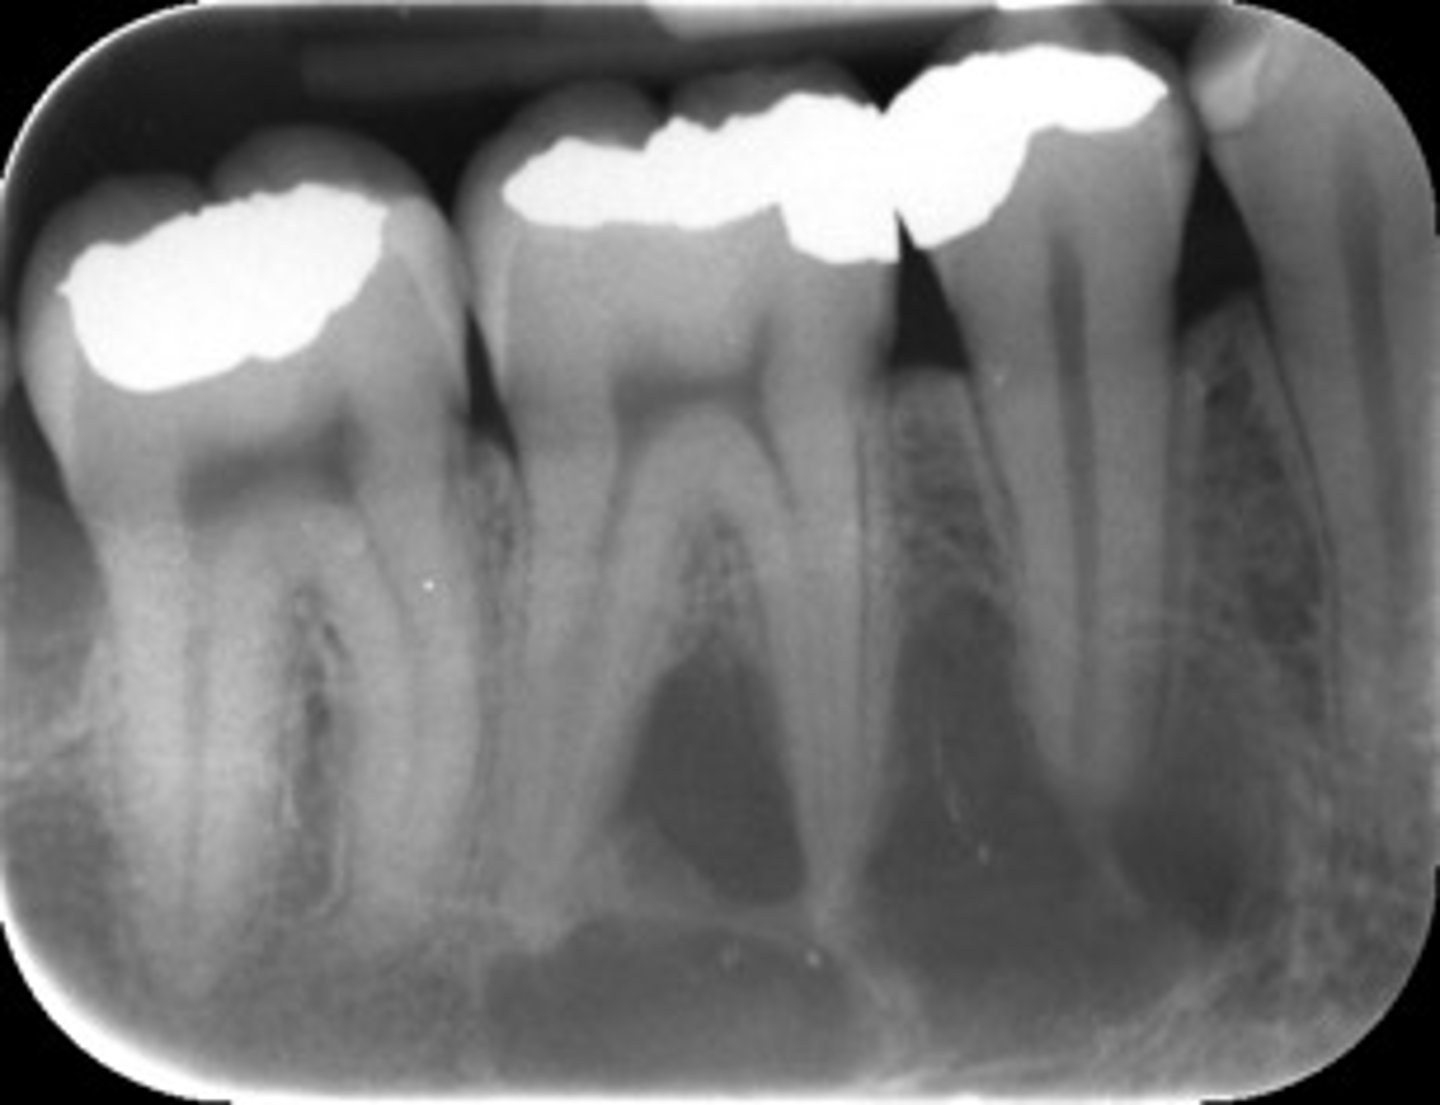

how would you describe the lesion?

A. well-defined, non corticated, periapical radiolucency associated with tooth number 14

B. ill-defined, non corticated, periapical radiolucency associated with tooth number 14

C. well-defined, corticated, pericoronal lesion with radiopaque flecks associated with an impacted tooth

D. well-defined, corticated, pericoronal radiopacity associated with an impacted tooth

What category would you put this lesion into?

Benign odontogenic tumor/cyst

all of the following could be a differential diagnosis for this lesion except?

A. AOT

B. calcifying epithelial odontogenic tumor (pindborg tumor)

C. Calcifying Epithelial odontogenic cyst (gorlin cyst)

D. osteosarcoma